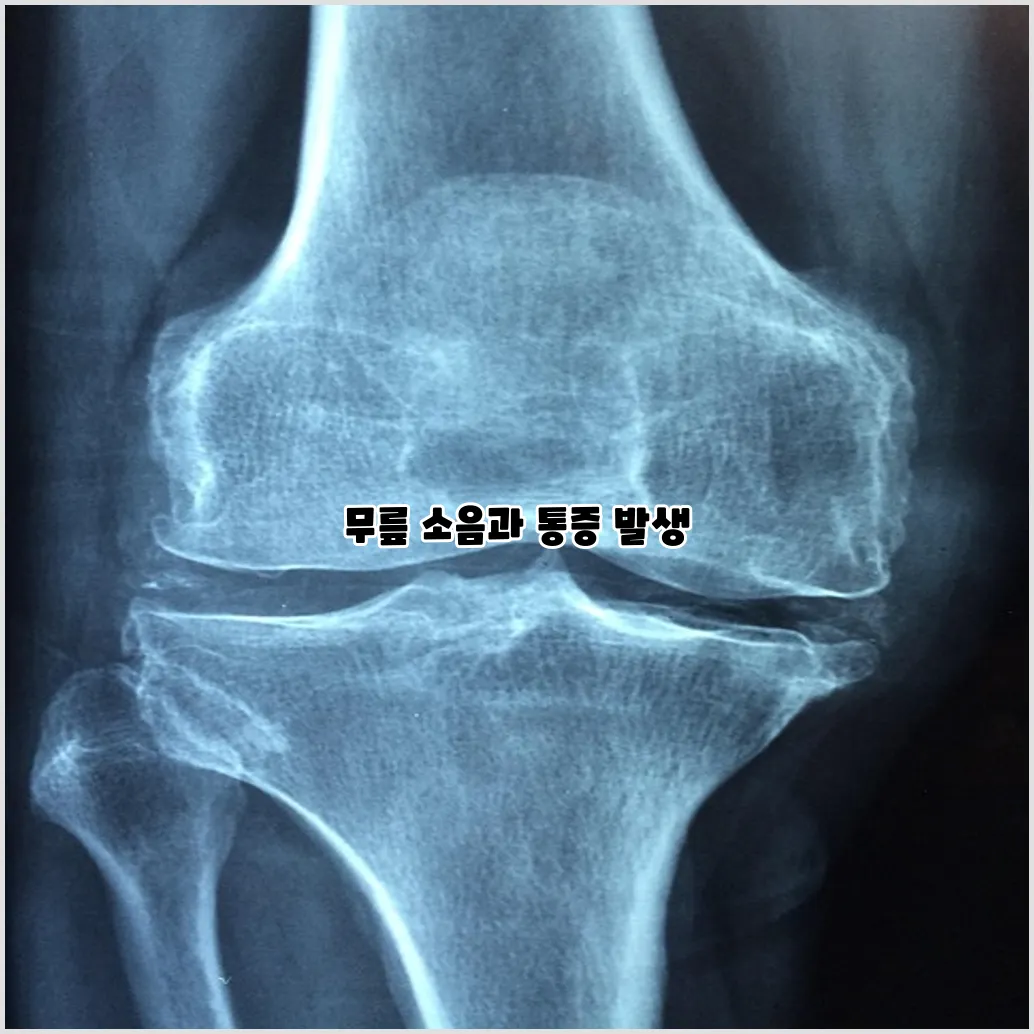

소리 및 크랙음

운동 도중 무릎에서 소리나 크랙음이 나는 경우도 흔한 증상이 될 수 있습니다. 이는 연골의 손상으로 인해 관절 내에서 비정상적인 마찰이 발생하기 때문입니다. 이 소음은 특별히 통증을 동반하지 않을 수도 있지만, 무릎의 상태가 좋지 않다는 신호일 수 있습니다.

무릎 연골 손상을 진단하기 위해서는 전문적인 검사가 필요합니다. 진단 과정에서는 의사의 신체 검사와 함께 X-선, MRI 등 다양한 영상 촬영이 이루어집니다. 이러한 검사는 무릎의 구조적 문제를 파악하는 데 중요한 역할을 합니다.